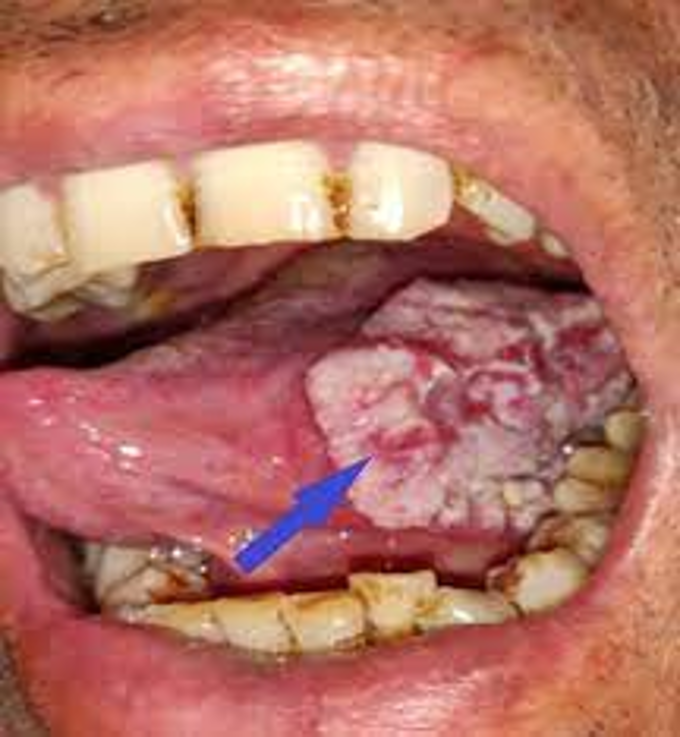

Ağız kanserleri sıklıkla 40 yaşın üzerinde ortaya çıkar ve erkeklerde oluşma olasılığı kadınlara oranla 2 kat fazladır. Ağız kanserlerinin oluştuğu en sık bölgeler; dil, ağız tabanı, dil köküne yakın yumuşak damak kısımları, dudaklar ve diş etleridir. Ağız kanseri erken dönemde teşhis edilerek tedavi sağlanmazsa yayılarak sürekli ağrı, fonksiyon kaybı, yüz ve ağız deformiteleri, hatta ölümlere neden olabilmektedir.

Ağız içinde veya etrafında, dil üzerinde beyaz veya kırmızı renkli alanlar şeklinde görülür. Eğer altta yatan sebep bir HPV virüsüne bağlı bir lezyon ise daha çok kondilom, siğil şeklinde görülmektedir. Ağızda veya boğazda tekrarlayan kanamalar, seste boğukluk veya boğazda yutulamayan cisim hissi, çiğneme ve yutma güçlüğü, dil ve çene hareketlerinde zorlanma, dil veya ağzın diğer bölgelerinde his kaybı, uyuşukluk, ağızda kitle – lezyon hissi ağız ve dil kanserinin belirtilerinden olabilmektedir.

Dudakta büyüme: Dil ve dudak kanserlerinin çoğu geçmeyen yara ve şişliğe neden olur. Yara ve şişlikler iltihaplanmadıkça ağrısızdır. Kanama görülebilirse de sıklıkla hastalığın ileri dönemlerine kadar görülmez. Yara ya da şişlik boyundaki bir kitleye eşlik ederse bu son derece ciddiye alınmalıdır. Diş doktorunuz ya da doktorunuz biyopsi (doku örnekleme testi) gerekip gerekmediğini değerlendirip bu işlem için sizi bir baş boyun cerrahına sevk edebilir.